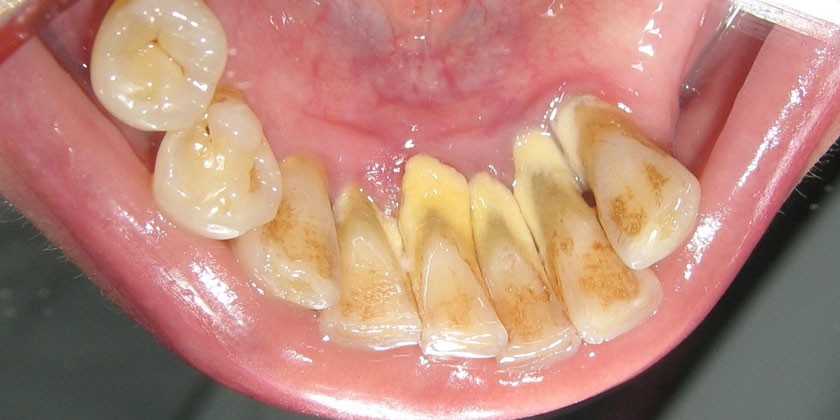

Общей причиной развития заболевания считается микробный налет на зубах. Он появляется при недостаточной гигиене или нарушении естественного очищения их поверхности. Этому способствует употребление большого количества сладостей и нехватка в рационе овощей и фруктов. Другие факторы риска возникновения гингивита:

- зубной налет или зубной камень;

- скопления мягкого микробного налета на зубах;

- зубной камень.

- мягкий зубной налет;

- твердые отложения на поверхности зубов;